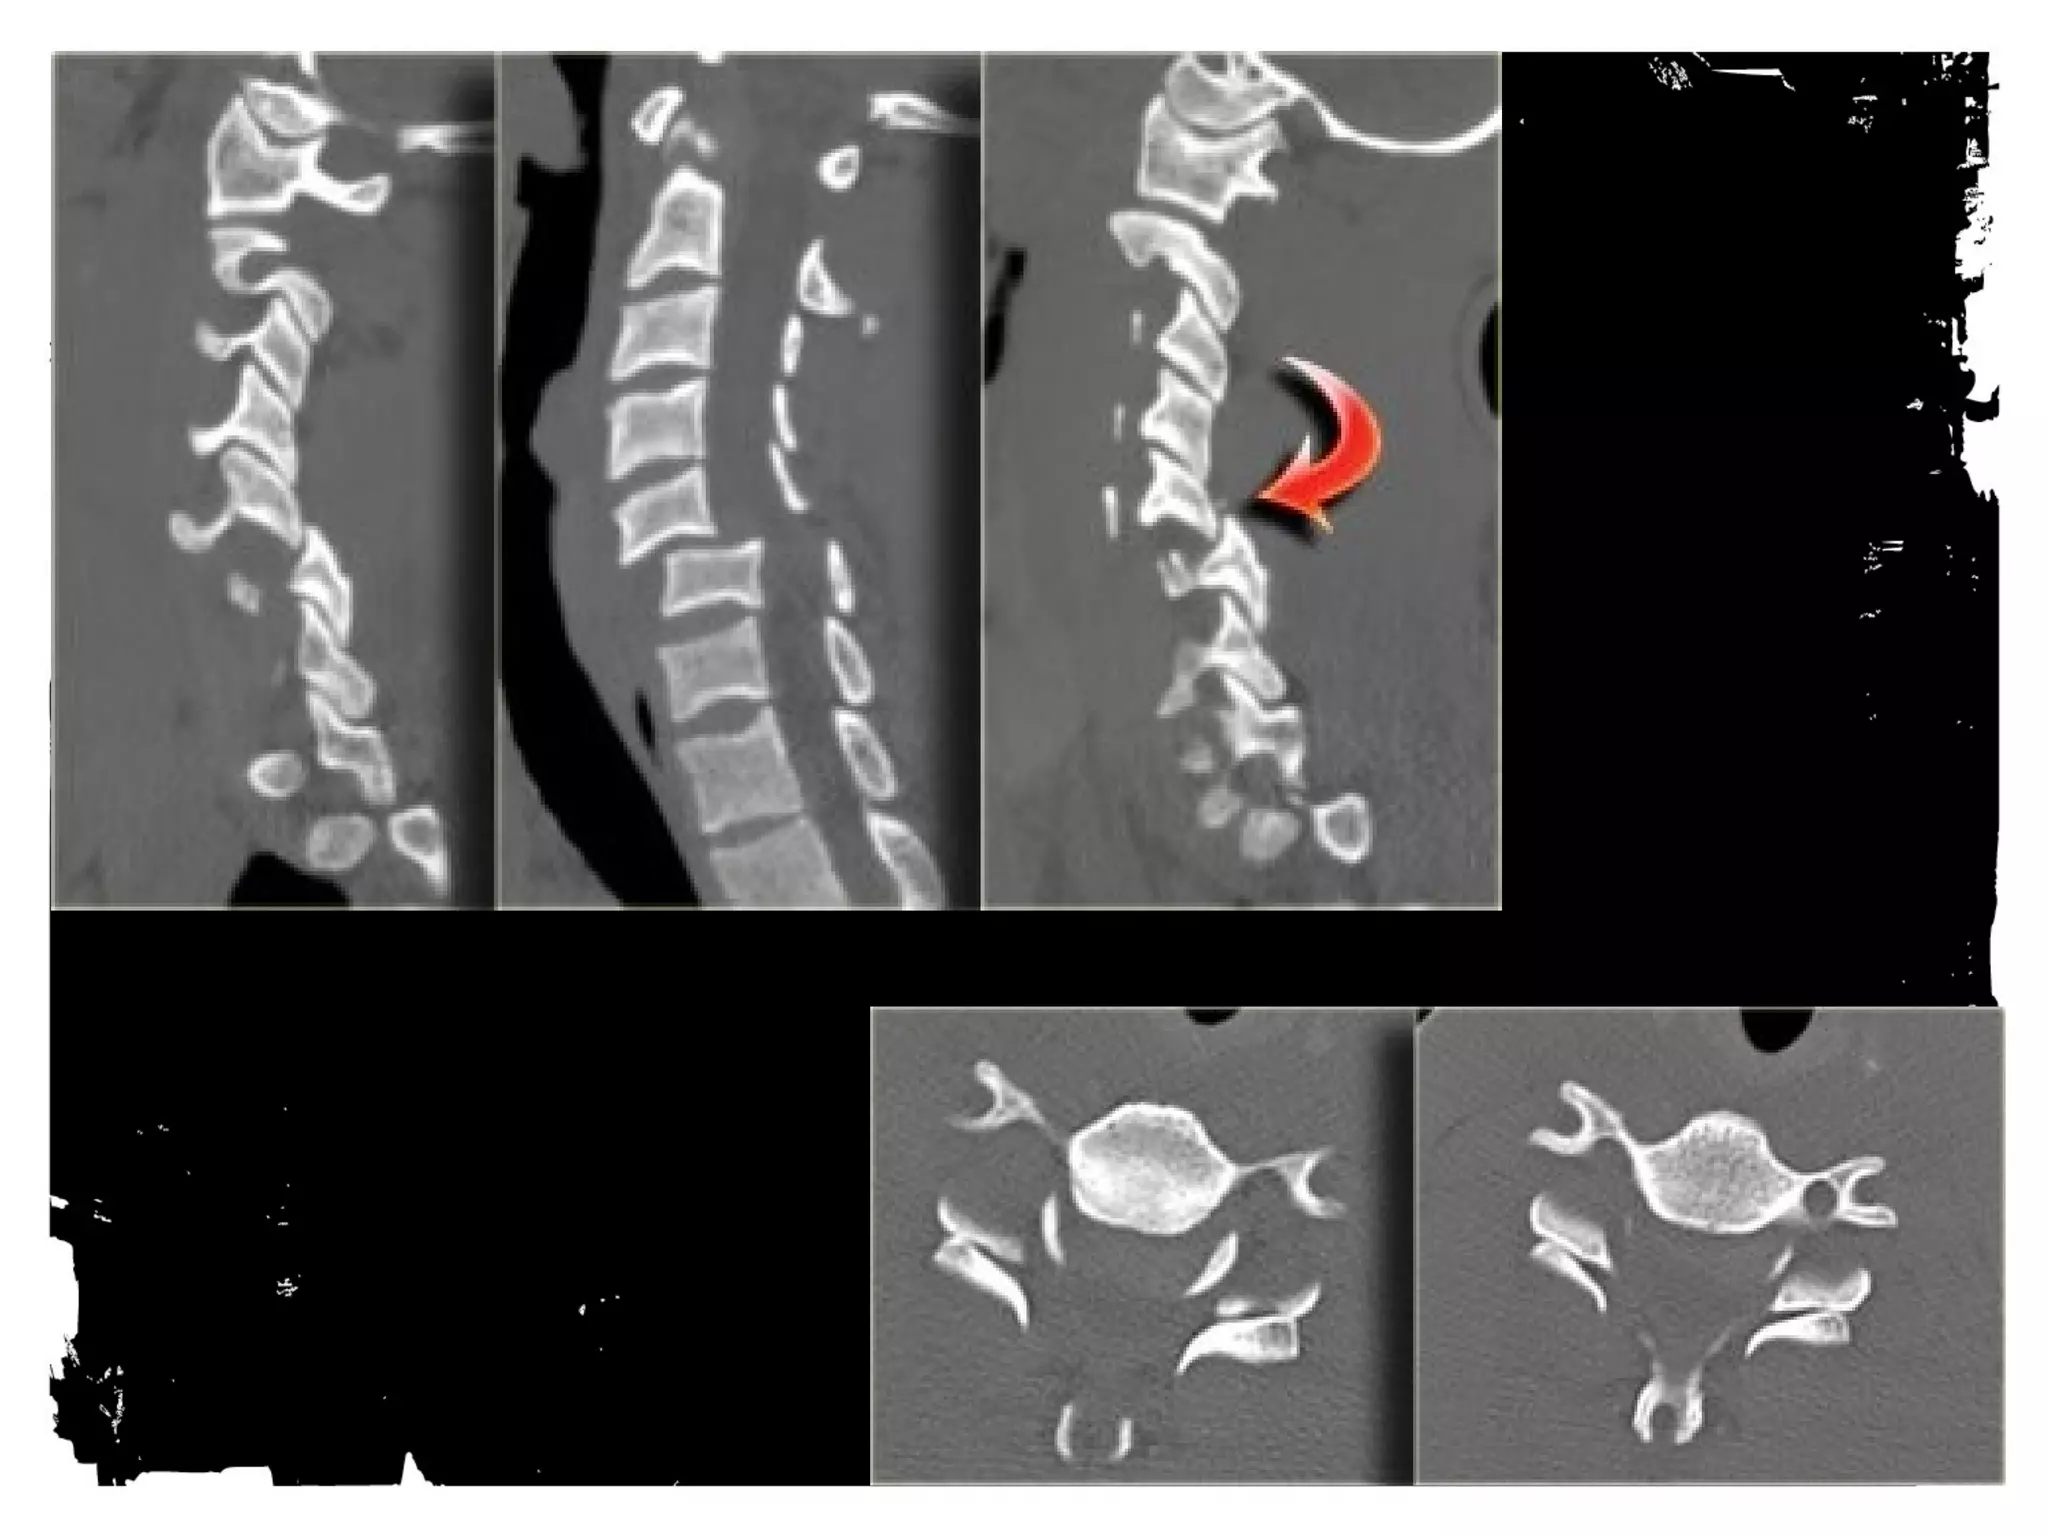

Case (4)

Flexion Tear Drop

Flexion+compression (MVA)

Teardrop fragment comes from the anteroinferior

aspect of the vertebral body

Larger posterior part displaced backward into the

spinal canal

Facets joints and interspinous distances usually

widened, disk space may be narrowed

70% of patients with neurologic injuries

Unstable fracture (complete disruption of ligaments

and anterior cord syndrome

Flexion Tear Drop Flexion+compression (MVA) Teardrop fragment comes from the anteroinferior aspect of the vertebral body Larger posterior part displaced backward into the spinal canal Facets joints and interspinous distances usually widened, disk space may be narrowed 70% of patients with neurologic injuries Unstable fracture (complete disruption of ligaments and anterior cord syndrome

• 112.